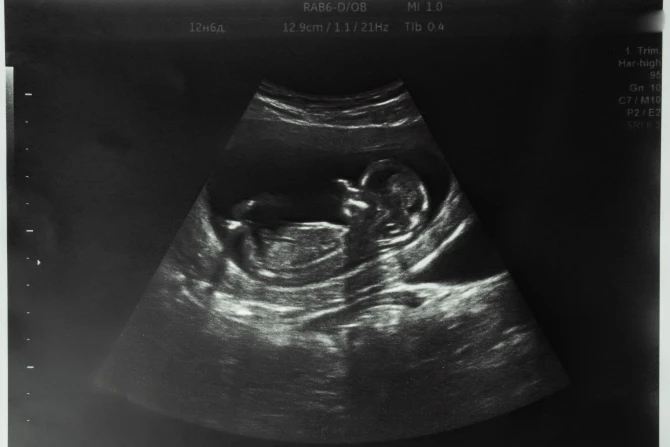

По ее словам, во многих случаях дети с генетическими аномалиями появляются на свет, а затем умирают от этих аномалий после рождения.

"Это дети, чьи аномалии достаточно значительны, чтобы они умерли в какой-то момент, - сказала она, - но вместо того, чтобы убивать их до рождения, они рождаются, а затем умирают после рождения, когда их начинают учитывать в нашей статистике".